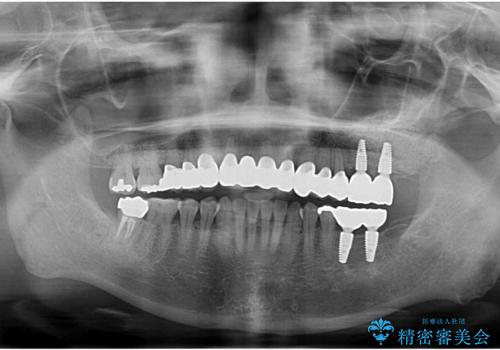

乳歯の残存 インプラントによる置き換え

- 大人になっても残存していた乳歯がグラグラし、痛くて噛めない 抜いて欲しいとの希望で来院されました。

歯根が吸収し残すことのできない乳歯を抜去後、隣の歯を削らずに済むインプラント治療で咬合機能の回復を計画します。

乳歯の抜去後、インプラントを用いてしっかりと咬合機能を回復することができました。